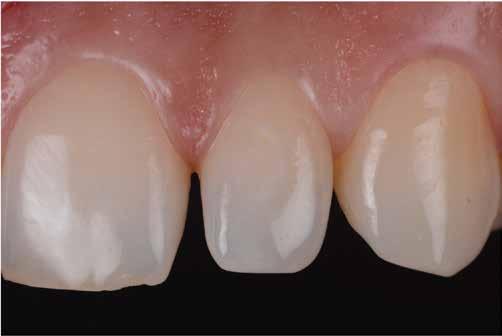

Nem volt kedvencem, de kevésbé kedveltem a hibrid technikát, ahol a palatális fal wax-uppal történő felépítése, majd a nyaki terület szabadkézi megerősítése után a restauráció többi részét mátrixszal lehetett kivitelezni (1. ábra). Bár a kezemben ez valahogy hatékony volt, mégis bonyolult volt.

1. ábra: A wax-up alapú technikák gyakori problémái, a szájpadlásfal apikális része hibás.

A szabadkézi technikák legnagyobb problémája kétségtelenül a nyaki pontosság hiánya és a túlnyúlások létrehozása. Számtalan olyan pácienst láttam, akiknek vérző ínyük volt, és nem tudtak megfelelően fogselymet használni. A másik gyakori probléma a klasszikus megközelítéssel kapcsolatban a végső forma volt. A dupla kiemelkedő profil miatt a végleges restaurációnak kellemetlen alakja volt (2-4. ábra). A kizárólag mátrixokkal történő közvetlen diasztémazárás problémái a nyaki szinten a túlkontúrozás és az alulkontúrozás, a diszkordáns kontaktpontok, az eltolt proximális kontaktok és a masszív többlettermelés. Hogy őszinte legyek, engem mindig is lebeszéltek arról, hogy ezzel a megközelítéssel próbálkozzam.

2-4. ábra: Gyakori problémák klasszikus megközelítéssel. 5. ábra: Tökéletes vészhelyzeti profil elülső szárnyas technikával. Dr. Jun Iwata, Japán jóvoltából.